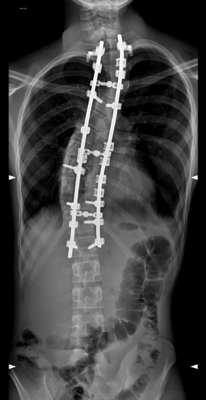

Aspect de scoliose thoracique pré et post-opératoire chez un adolescent de 15 ans